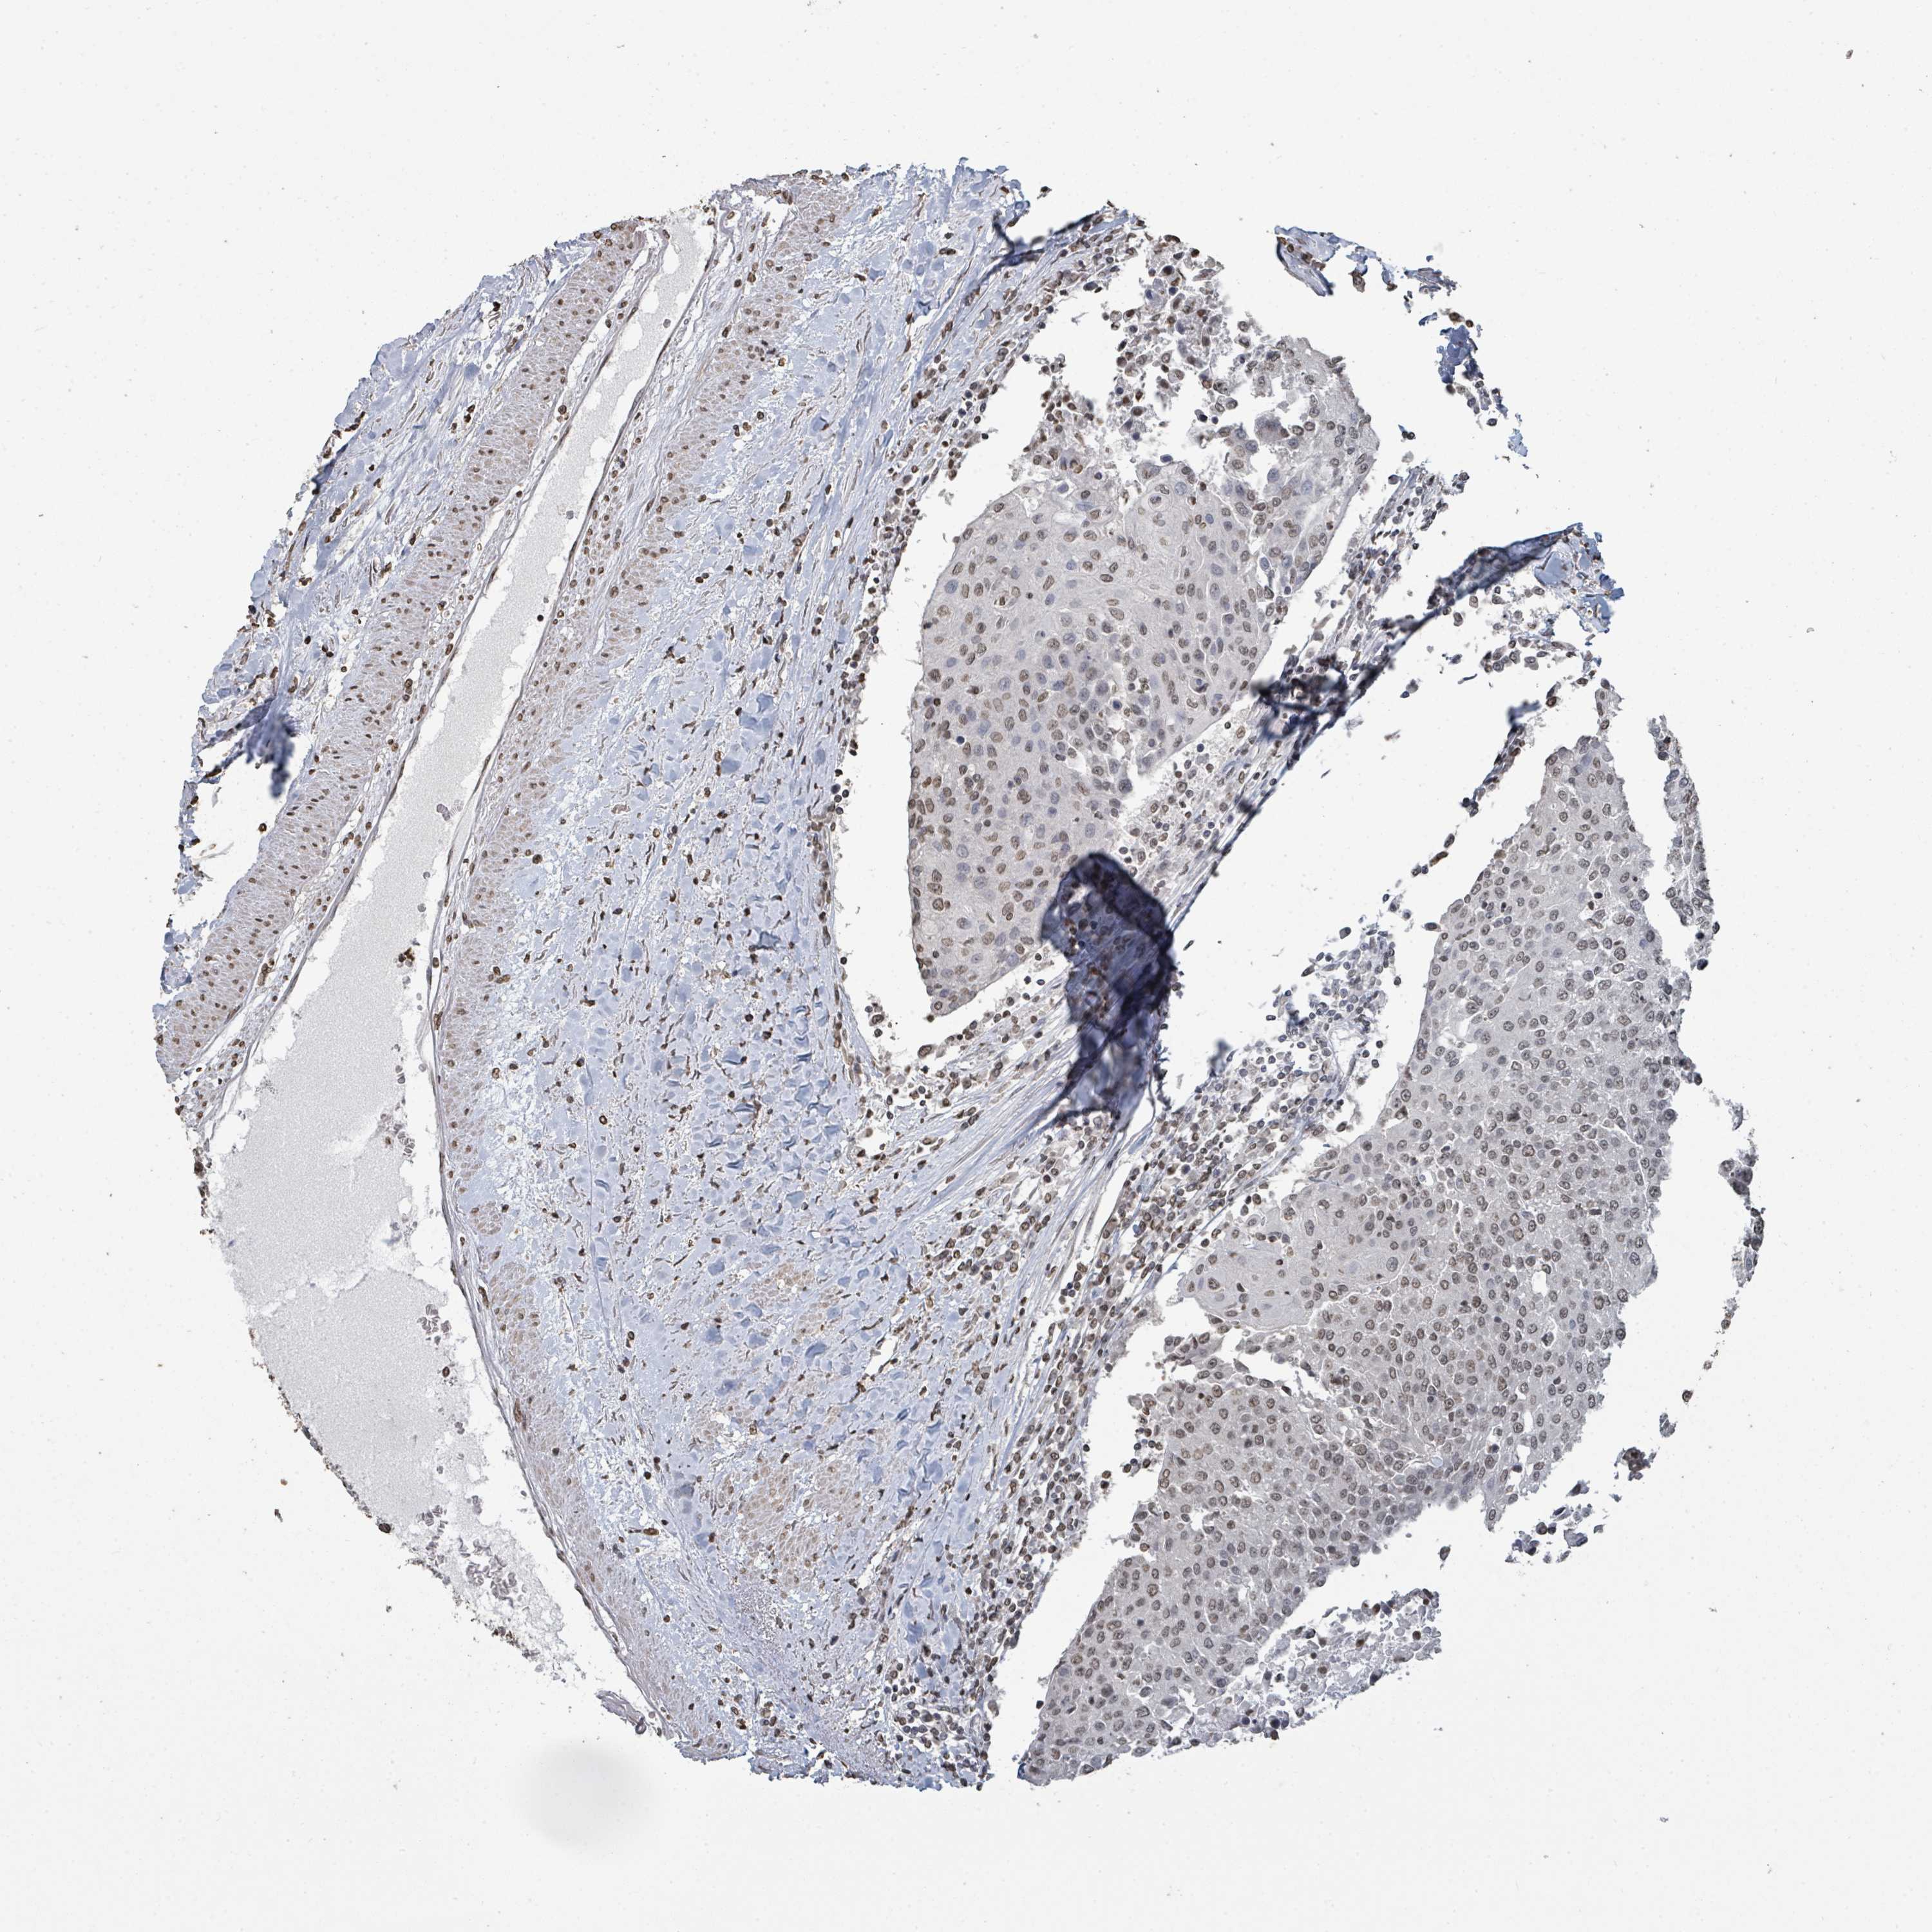

UROTHELIAL CANCER - Protein expressioni

A mouse-over function shows sample information and annotation data. Click on an image to view it in a full screen mode. Samples can be filtered based on level of antibody staining by selecting one or several of the following categories: high, medium, low and not detected. The assay and annotation is described here.

Note that samples used for immunohistochemistry by the Human Protein Atlas do not correspond to samples in the TCGA dataset.

Antibody stainingi

Antibody staining in the annotated cell types in the current human tissue is reported as not detected, low, medium, or high, based on conventional immunohistochemistry profiling in selected tissues. This score is based on the combination of the staining intensity and fraction of stained cells.

Each image is clickable and will lead to virtual microscopy that enables deeper exploration of all samples and also displays staining intensity scores, fraction scores and subcellular localization as well as patient and tissue information for each sample.

Antibody HPA046775

Antibody HPA050633

Urothelial carcinoma, High grade

Urothelial carcinoma, Low grade

Urothelial carcinoma, NOS